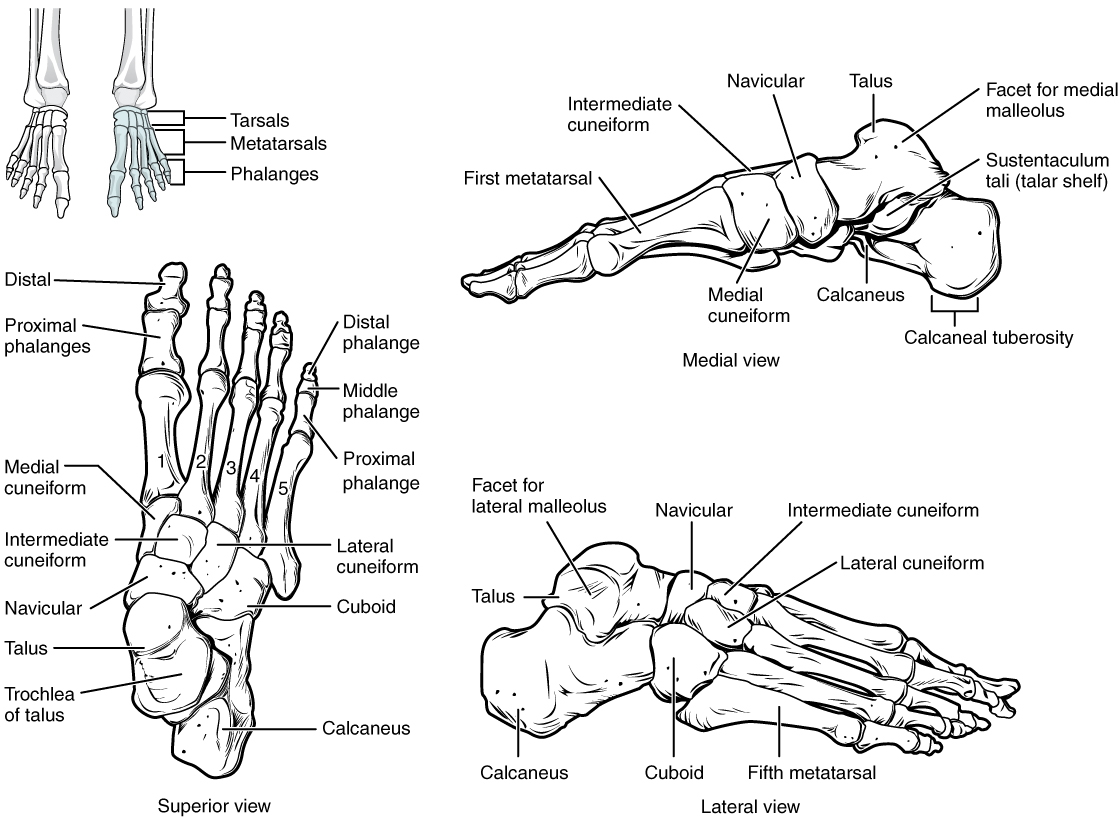

what are the bones of the lower leg?

tibia

fibula

what are the tarsal bones?

cuneiforms

cuboid

navicular

calcaneus

talus

what are the bones of the foot?

metatarsals

phalanges

what do the metatarsals look like?

what are the landmarks of the metatarsals?

base

shaft

head

how are the phalanges of the foot based on?

distal

middle

proximal

what are the landmarks of the phalanges of the foot?

base

shaft

head